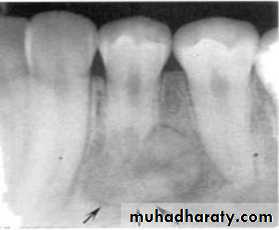

• A lesion (developmental salivary gland

• defect) below the IAC• (non- odontogenic origin).